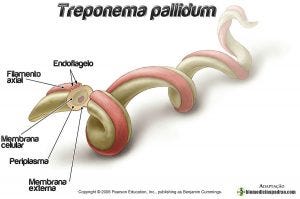

Karakteristik treponema pallidum, morfologi, habitat / Biologi | Thpanorama - Jadikan diri Anda lebih baik hari ini!

Karakteristik treponema pallidum, morfologi, habitat / Biologi | Thpanorama - Jadikan diri Anda lebih baik hari ini!

1. TREPONEMA PALLIDUM - PDF Free Download

1. TREPONEMA PALLIDUM - PDF Free Download

Triponema P - [PDF Document]

Triponema P - [PDF Document]